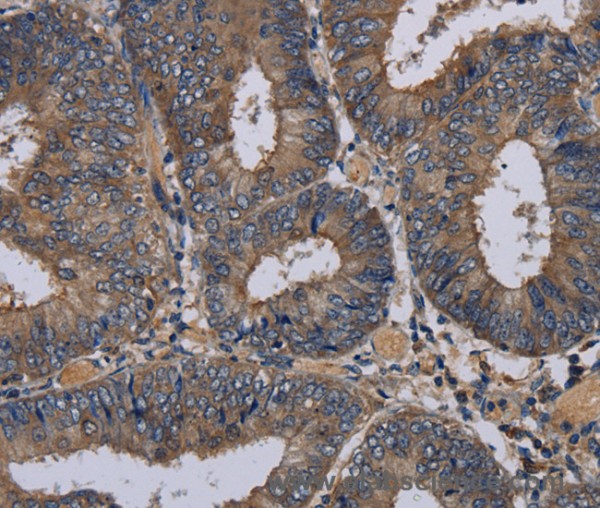

This gene encodes a member of the nectin family of proteins, which function as adhesion molecules at adherens junctions. This family member interacts with other nectin-like proteins and with afadin, a filamentous actin-binding protein involved in the regulation of directional motility, cell proliferation and survival. This gene plays a role in ocular development involving the ciliary body. Mutations in this gene are believed to result in congenital ocular defects. Alternative splicing results in multiple transcript variants. Protein function: Plays a role in cell-cell adhesion through heterophilic trans-interactions with nectin-like proteins or nectins, such as trans-interaction with NECTIN2 at Sertoli-spermatid junctions. Trans-interaction with PVR induces activation of CDC42 and RAC small G proteins through common signaling molecules such as SRC and RAP1. Also involved in the formation of cell-cell junctions, including adherens junctions and synapses. Induces endocytosis- mediated down-regulation of PVR from the cell surface, resulting in reduction of cell movement and proliferation. Plays a role in the morphology of the ciliary body. [The UniProt Consortium]